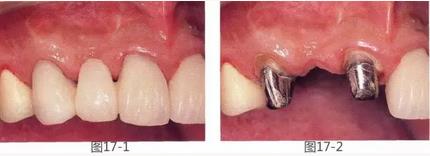

圖16-1,2  術(shù)前。有垂直以及水平牙槽嵴吸收。另外,左下2,3有深度牙周袋,附著齦也不足。

圖17-1,2  術(shù)前。右上2的橋體部唇側(cè)存在凹陷。